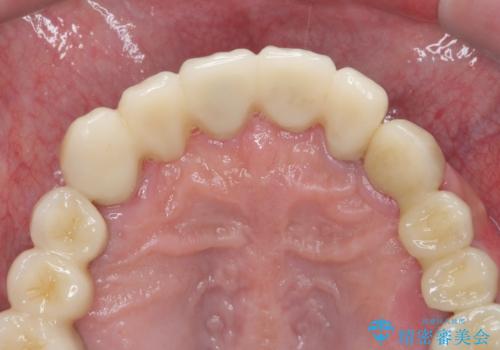

歯周病治療を伴う前歯審美セラミック治療

歯周外科を行ったことで非常に安定した歯周環境となり、引き締まった歯ぐきとなりました。